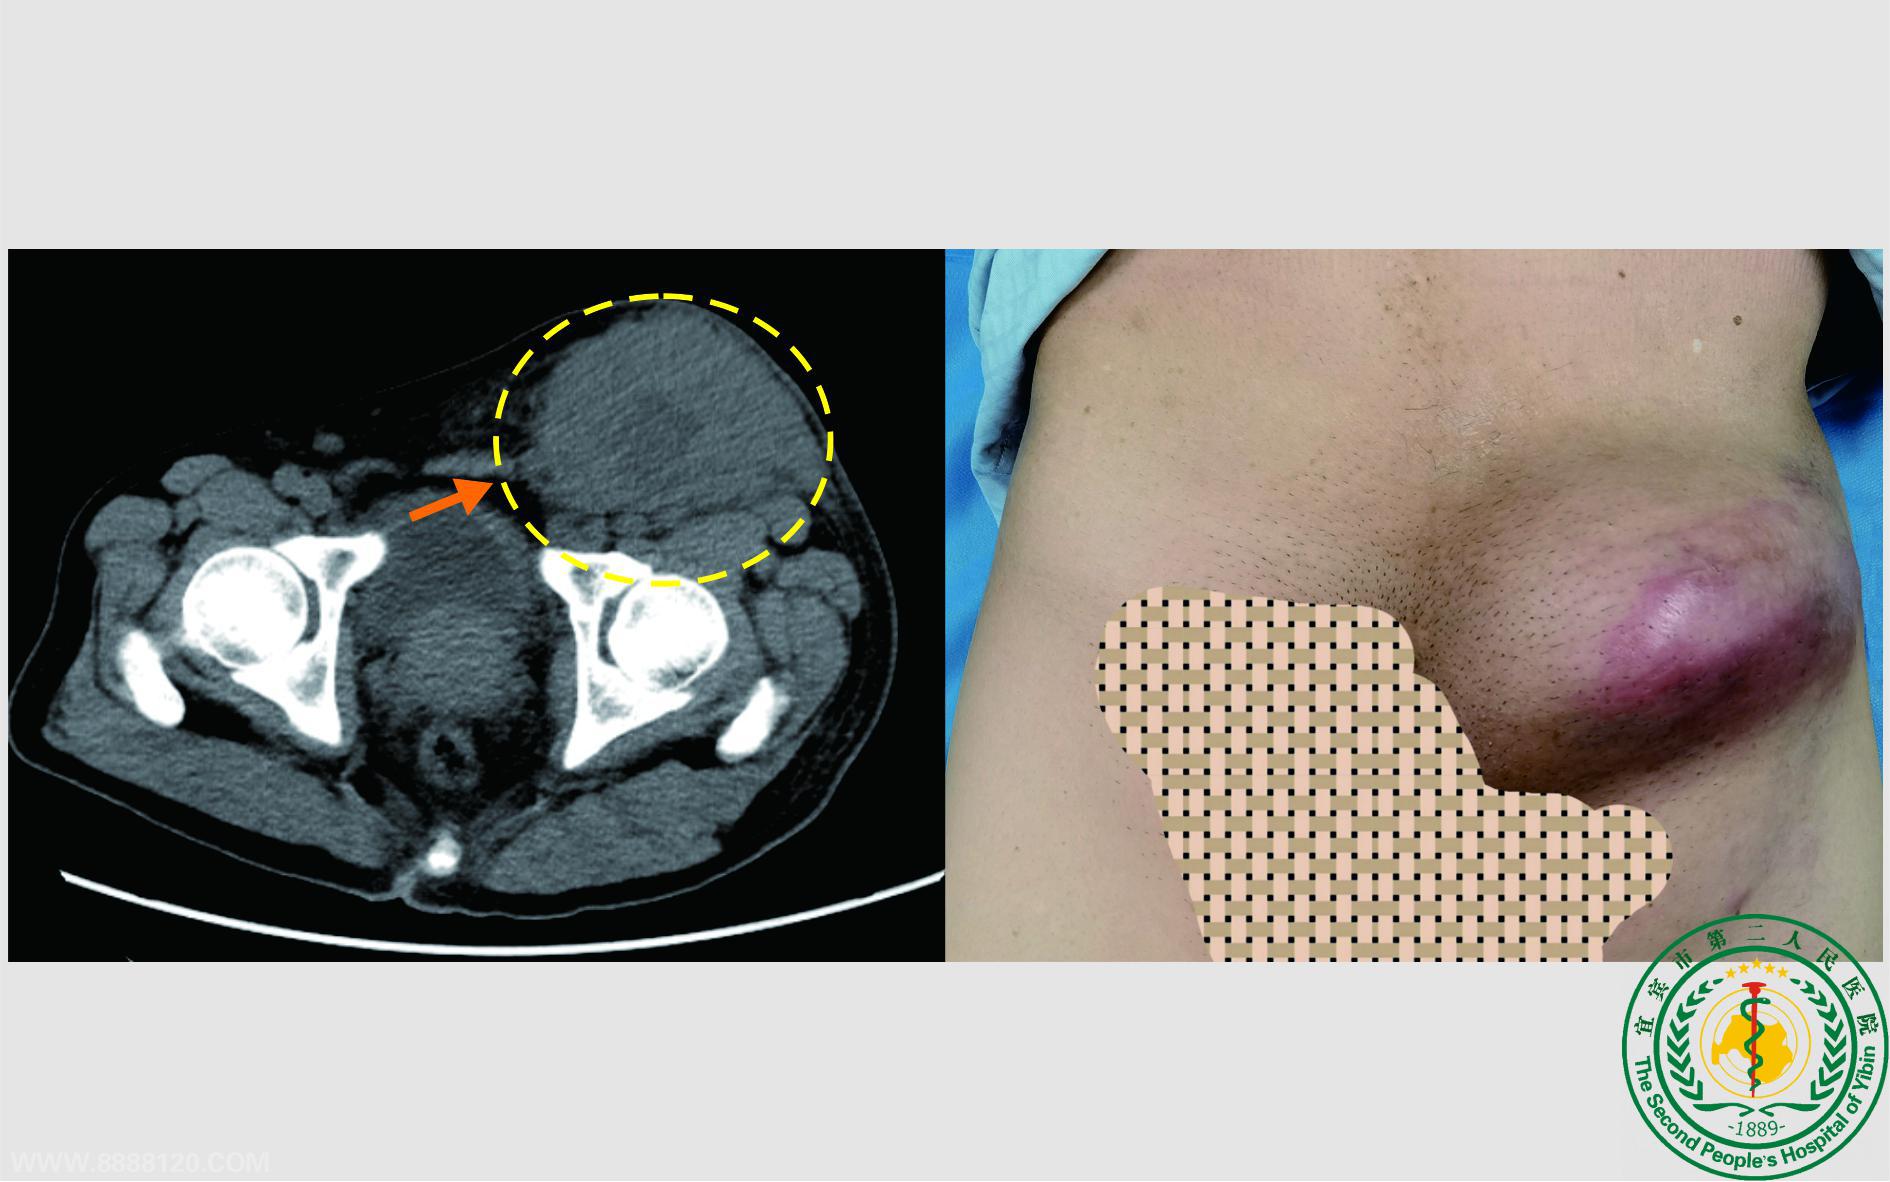

患者张大爷,广西北海合浦县人,因腹股沟肿瘤于当地县医院治疗,因肿瘤过大,当地医院拒绝给予安排手术,建议上级医院治疗。但当地上级医院仍因肿瘤过大拒绝给予安排。患者家属通过自媒体平台寻找治疗方案时,发现宜宾市第二人民医院胃肠疝外科罗坤主治医师曾多次成功施行该项手术。于是,家属通过网络多次咨询罗医生该疾病的相关问题,并到宜宾市第二人民医院门诊求诊,但一行人到宜宾后发现罗医生在雅江县人民医院进行对口帮扶工作,遂全家人决定在宜宾市第二人民医院完善部分检查后再到雅江县人民医院就诊。到达雅江后,罗医生热情的接待了患者及家属,并告知其该病的可能诊断与治疗规范,患者和家属在反复商量后决定进行手术治疗。20231124日,在完善相关检查后,罗医生在全麻下为其实施了左侧腹股沟肿瘤切除,手术顺利,一周后患者康复出院。住院期间罗医生婉拒患者家属5000元红包,患者家属为了感谢罗医生及雅江县人民医院,赠送锦旗两面。